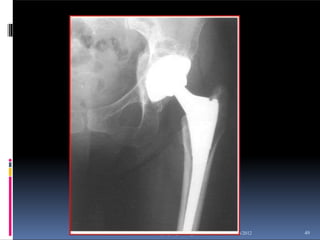

 age more than 60 years

normal hip- Hemiarthroplasty with Austin-

Moore prosthesis.

 Indications for hemiarthroplasty

 Comminuted, displaced

femoral neck fracture in the

elderly

 Pathologic fracture

 Poor medical condition

 Poorer ambulatory status before

fracture

 Neurologic condition (dementia,

ataxia, hemiplegia, parkinsonism)